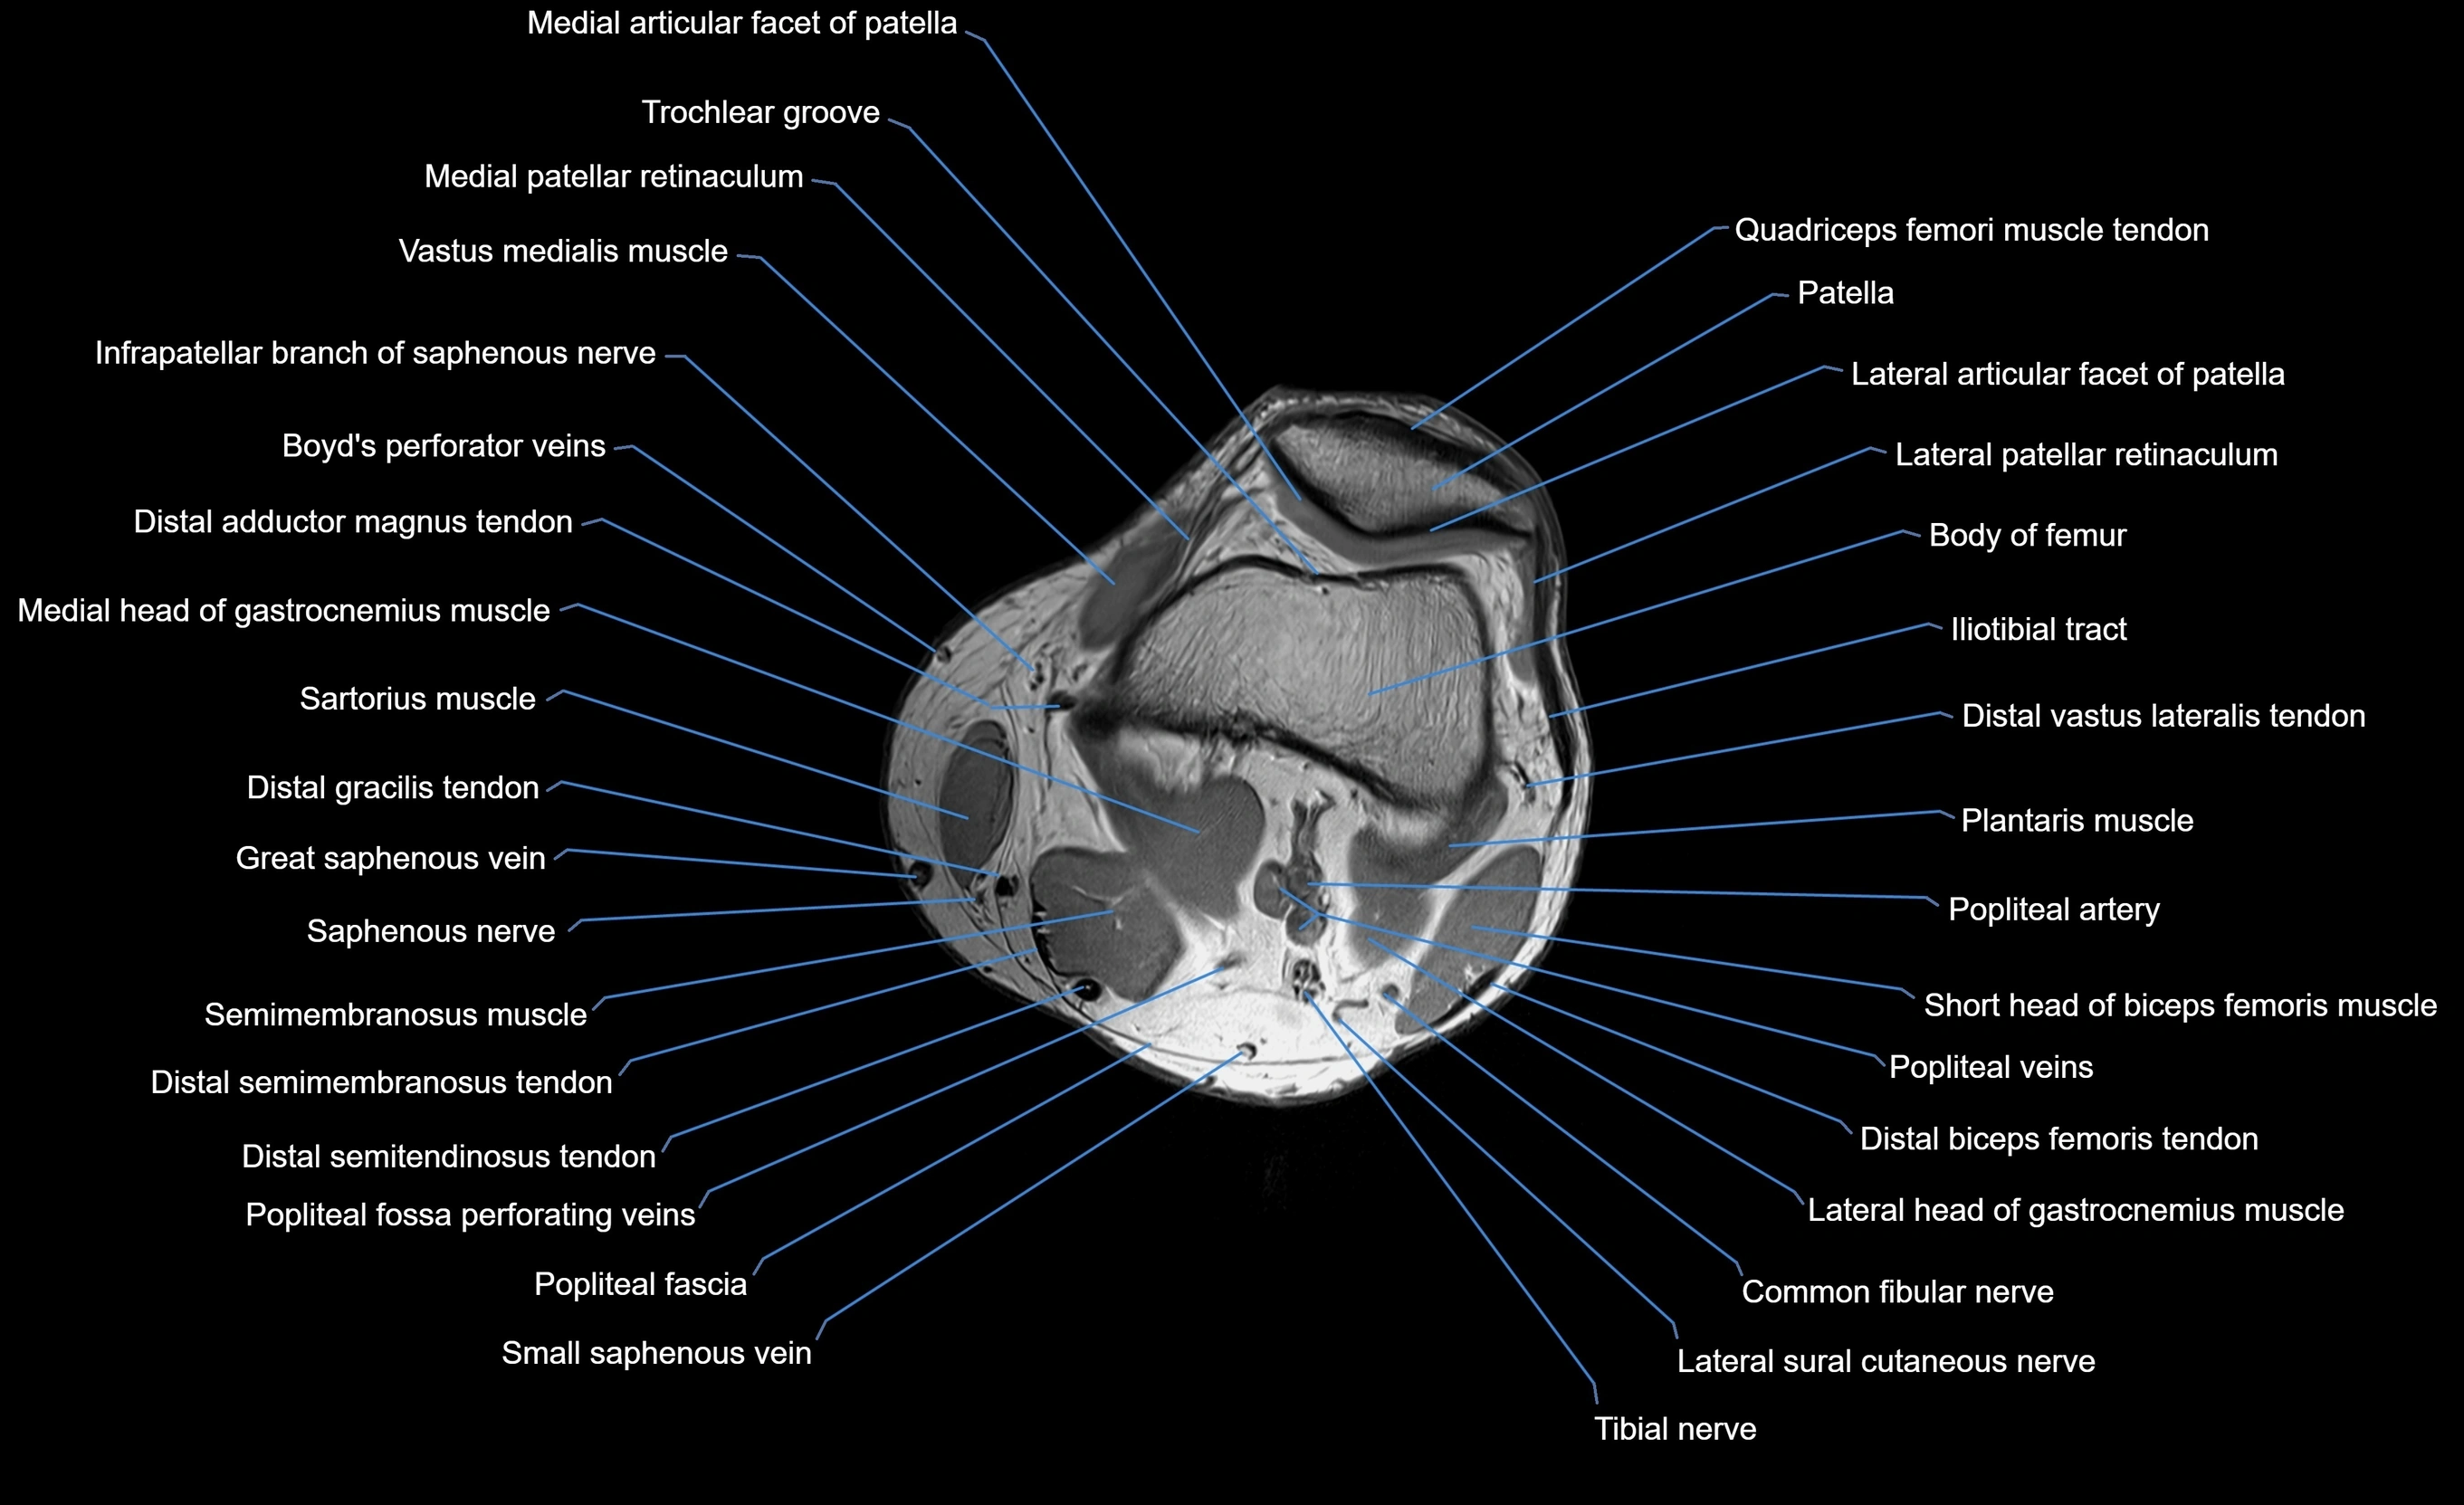

MRI image